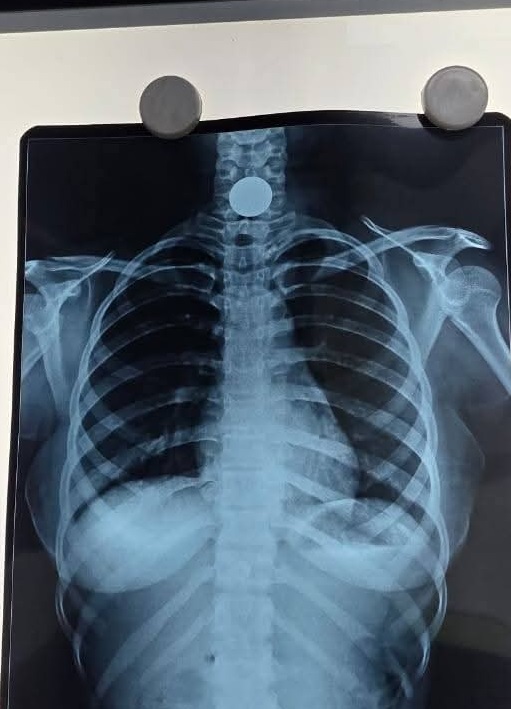

छतरपुर (राजेश चौरसिया): छतरपुर के प्रसिद्ध सर्जन डॉक्टर मनोज चौधरी को कौन नहीं जानता है, मनोज डॉक्टर सिक्का के नाम से भी जाने जाते है। एक बार फिर मनोज चौधरी चर्चा में है क्योंकि अबकी बार इन्होंने 5 रुपये या एक रुपये का नहीं 10 रुपये का सिक्का बिना ऑपरेशन करके निकाला है। जिला अस्पताल में वरिष्ठ सर्जन पद पर पदस्थ डॉक्टर मनोज चौधरी ने हाल ही में 15 वर्षीया किशोरी के गले से फंसा हुआ सिक्का निकाला है और अब वह एकदम स्वस्थ है।

बता दें कि गले में फंसे सिक्का निकालने में महारत हासिल प्राप्त जिला चिकित्सालय छतरपुर के जाने माने डॉक्टर मनोज चौधरी अस्पताल में चिकित्सक के पद पर पदस्थ हैं । मनोज ने 15 वर्षीया किशोरी के गले में फंसे सिक्के को चंद मिनटों में बिना किसी सर्जरी या ऑपरेशन के निकाल दिया है।किशोरी के चेहरे पर इसकी खुशी साफ देखी जा सकती है। आपको बता दें कि डॉ चौधरी गले में फंसे सिक्के निकालकर डॉक्टरी पेशे को तो गौरान्वित कर ही रहे हैं, साथ ही मानवता को भी चरितार्थ कर रहे हैं।